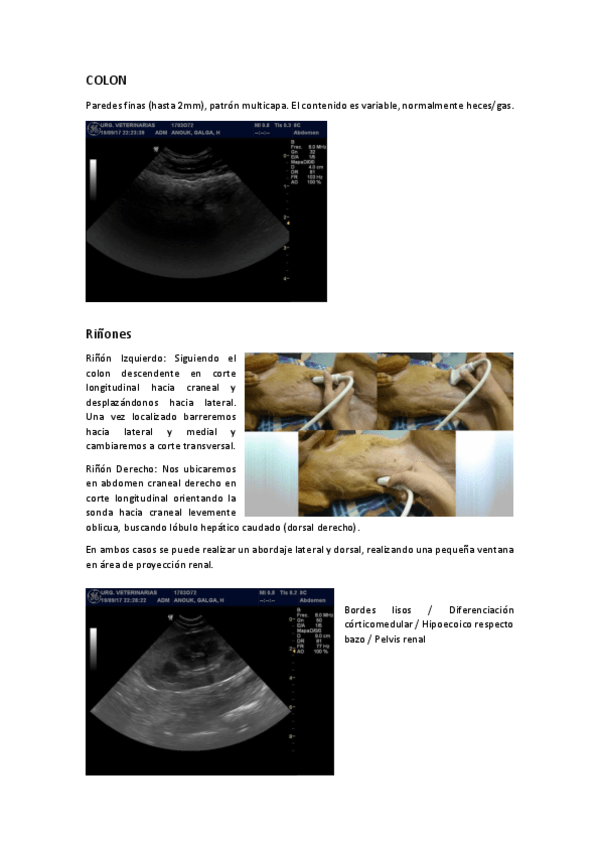

3.1.-ECOGRAFIA-ABDOMINAL.pdf